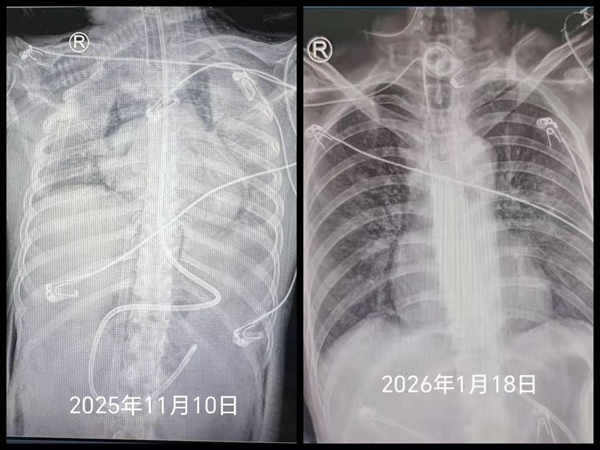

女孩免疫力极度低下,快速锁定致病菌、精准施治成为遏制病情的关键。罗红教授带领重症肺炎MDT多学科诊疗团队,集结感染、影像、检验、临床药学等领域专家,围绕肺部影像分析、微生物筛查等核心问题开展十余次讨论,通过精准抗感染与免疫调节双重干预,让女孩肺部病灶逐步吸收,大白肺状态得到有效逆转。同时,针对女孩长期留置多重侵入性管路、院内感染风险高的问题,唐莉护士长带领护理团队建立每日感染风险排查清单,提前预判、尽早干预,实现多重管路留置期间零院内感染。

46天撤离ECMO,65天撤离呼吸机,70余天实现简单交流,这场跨越两个多月的生命救援,是湘雅二医院现代医学技术与多学科协作能力的集中展现,也是22岁生命坚韧的见证,更是医者仁心的真实写照。